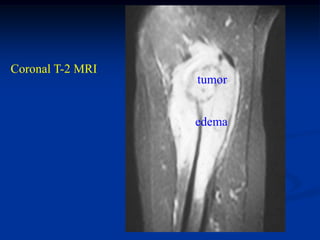

Case # 124.1                    AP and lat x-ray

50 year male with chondromyxoid fibroma proximal

tibia with 6 months of a tender tumor mass anterior tibia

Axial Gad MRI